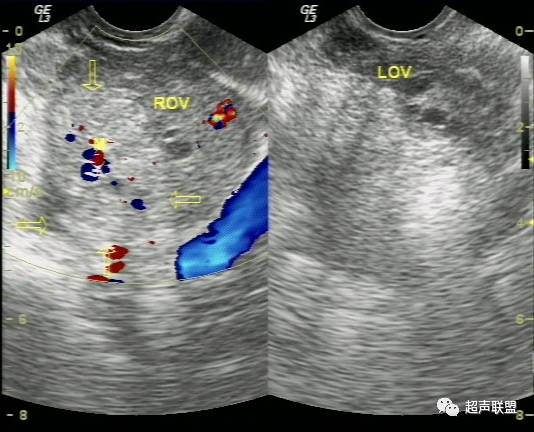

超声检查声像图特点:

(2)一侧附件区可探及不均质包块,包块形态欠规则,边界不清楚,回声紊乱。

(2)卵巢黄体破裂一般无盆腔包块,但如于黄体附近形成血凝块,与破裂黄体混合形成包块时,是最不易与宫外孕破裂鉴别的疾病之一,特别是与卵巢内异位妊娠破裂不易鉴别。因其声像图均表现为附件区混合性包块,阴道检查则发现包块均位于卵巢内,盆腔液性暗区均有密集点状回声等出血征象。但黄体破裂子宫大小正常,子宫内膜为分泌期内膜,而无蜕膜反应性增厚。其临床资料无停经史,破裂腹痛时多发生于月经中后期,常因腹部重击、及妇科检查引起。盆腹腔积液相对较少,而尿或血HCG检查常阴性。

(4)卵巢囊肿破裂,患者过去多有囊肿病史,突发剧烈腹痛亦多有重击、及妇科检查等诱因。巧克力囊肿则多有痛经病史,由于其囊壁较厚一般不容易破裂,但当月经期出血量多时仍可以破裂。超声检查发现其子宫大小亦多正常,子宫内膜不厚,患者亦无停经史,尿HCG检查阴性。  总之,宫外孕破裂出血是妇产科最常见的急腹症之一。出血量大者,病情特别危急,需要立即做出诊断和鉴别诊断,以便采取适当而有效的治疗措施。对于一个临床主要表现为下腹剧烈疼痛,超声表现为附件或盆腔混合性包块,伴有盆腔甚至腹腔积液的妇科急症患者,检查者应该想到上述疾病。超声声像图注意观察子宫大小、子宫内膜厚度、盆腔积液的内部回声等。并尽可能详细询问月经史、性生活史及临床病史,结合尿或血HCG检查、血常规检查等,进行综合分析判断。随着超声仪技术的发展,阴道彩色多普勒检查的应用,宫外孕包块内滋养层血流的检测,将更有助于宫外孕破裂的诊断及鉴别诊断。

宫外孕破裂出血是妇产科最常见的急腹症之一。出血量大者,病情特别危急,需要立即作出诊断和鉴别诊断,以便采取适当而有效的治疗措施。对于一个临床主要表现为下腹剧痛,超声表现为:子宫轻度增大,子宫内膜不同程度增厚,宫内未见妊娠囊;一侧附件区可探及不均质包块,包块形态欠规则,边界不清楚,回声紊乱;陶氏窝可见多少不一不规则的液性暗区,暗区中有密集点状回声。盆腔甚至腹腔积液的妇产科急症患者。检查者应该想到上述疾病。并尽可能详细询问月经史、性生活史及临床病史,结合尿或血HCG检查、血常规检查等,进行综合分析判断。随着超声仪技术的发展,阴道彩色多普勒检查的应用,宫外孕包块内滋养层血流的检测,将更有助于宫外孕破裂的诊断及鉴别诊断。